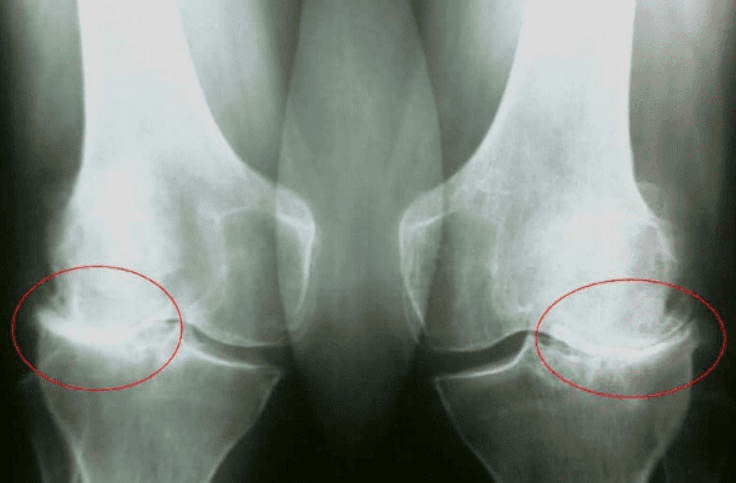

Martin Repko: Hlavní komplikace patologie kloubů zahrnují změnu tvaru kloubu, výrazné omezení pohybu a ztuhlost, která kloub zcela imobilizuje, často v nesprávné pozici.

V případě neúplného ohybu a natažení kloubů se mění osy končetin, podél kterých se rozkládá hlavní mechanická zátěž těla. V důsledku systematického narušení správné osy končetiny se zvyšuje zatížení ostatních kloubů, což vede k sekundárním degenerativním změnám.

Týká se to především těžkých kloubů: kolenních, kyčelních a kotníkových.